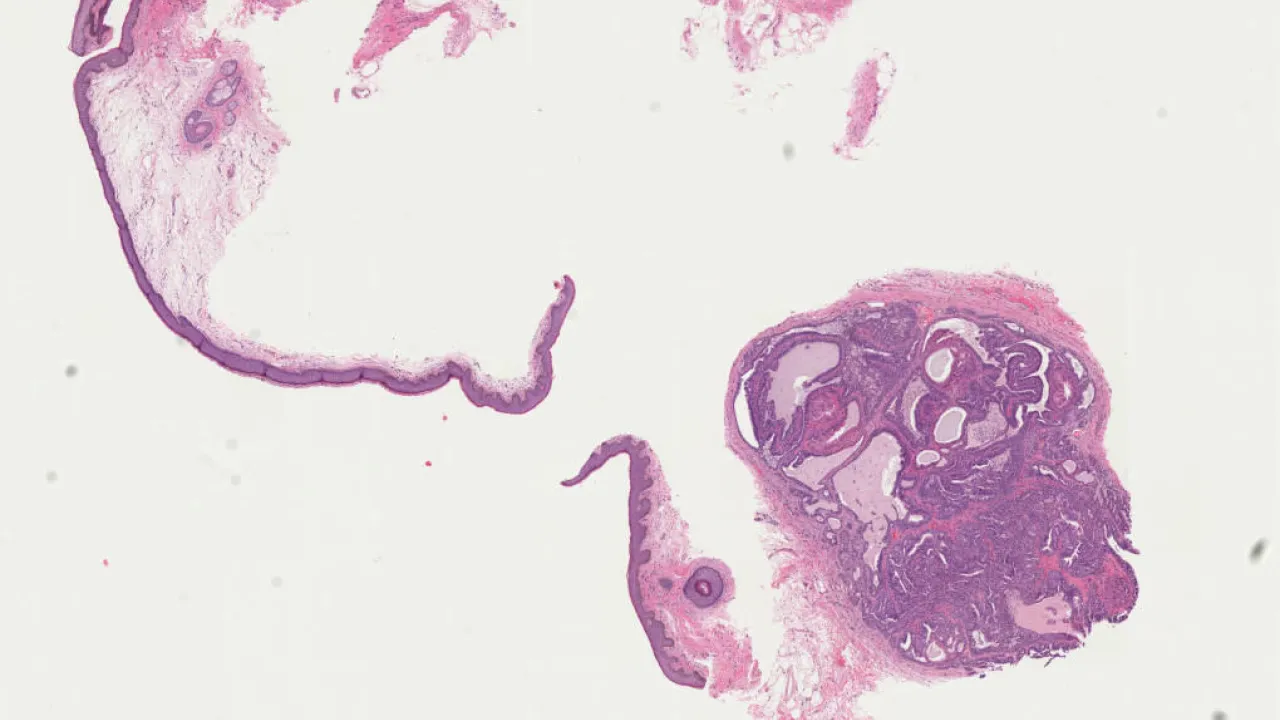

Vulva, Papillary hiradenoma